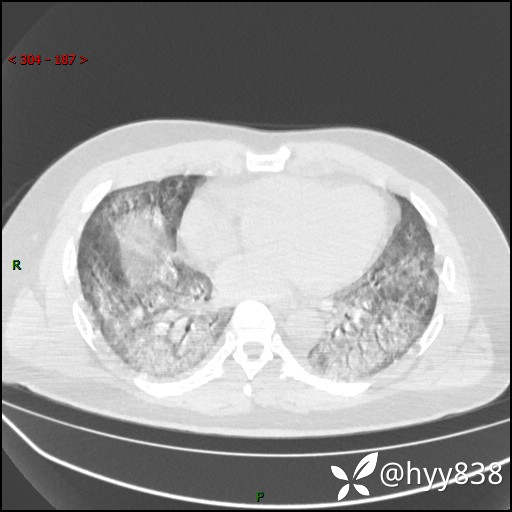

第二次CT(7天后)